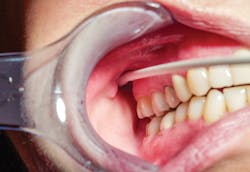

The injection site or needle insertion point is the buccal mucosa between the medial surface of the mandibular ramus and the maxillary tuberosity, with the syringe parallel to the maxillary occlusal plane (see Figure 5). Thus this injection is administered at a site more inferior than the G-G block but more superior than the IA block.

Figure 5: Injection site for the Vazirani-Akinosi mandibular block is palpated at the buccal mucosa with the injection height at the same height as the mucogingival junction of the maxillary third or second molar directly across from the tooth.2,3 (courtesy of Elsevier)